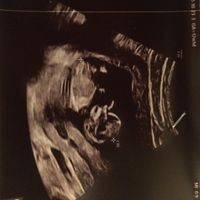

Ciao ragazze, sono a 29 settimane e il mio piccolo è ancora podalico, era così anche alla 25, invece alla morfologica era cefalico. Nelle ultime 2 eco aveva anche le manine sul viso e non siamo...